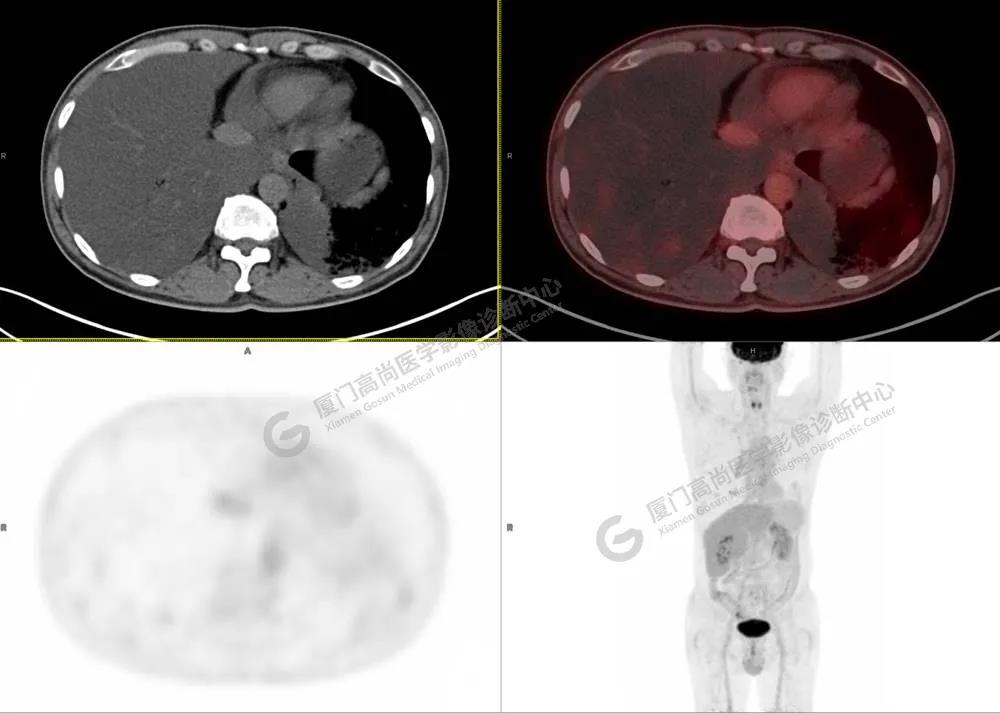

PET/CT影像圖

圖4

PET/CT所見(jiàn):雙肺大片實(shí)變影及磨玻璃影,部分呈地圖樣改變,累及右肺尖,部分放射性攝取輕微增高,SUVmax 1.77,其內(nèi)見(jiàn)多發(fā)支氣管充氣征象。

影像診斷: 雙肺大片實(shí)變影及磨玻璃影,大部分代謝不高,局部代謝輕微增高,考慮肺泡蛋白沉積癥,建議病理學(xué)檢查或肺泡灌洗物檢查。

影像學(xué)表現(xiàn):HRCT上雙肺斑片影,以肺門為中心呈蝶翼狀對(duì)稱分布;病變可隨機(jī)分布在中央?yún)^(qū)、周圍區(qū)或全肺葉,病灶與正常分組織分界清楚,呈典型“地圖樣”改變;有支氣管充氣征,但表現(xiàn)為充氣支氣管細(xì)小且數(shù)量及分布稀少;“碎石路”征由彌漫性磨玻璃影及內(nèi)部網(wǎng)格樣小葉間隔增厚組成(鋪路石樣表現(xiàn))。無(wú)空洞、蜂窩狀改變、淋巴結(jié)腫大、胸腔積液及明顯實(shí)變等。肺內(nèi)病灶累及范圍、磨玻璃密度高低與PAP患者的病情嚴(yán)重程度相關(guān),嚴(yán)重者病灶累及全肺,同時(shí)出現(xiàn)肺內(nèi)大片實(shí)變,并見(jiàn)充氣支氣管征象。PAP影像學(xué)表現(xiàn)程度與臨床癥狀、體征嚴(yán)重程度不成比例,表現(xiàn)為影像改變重,臨床癥狀輕。